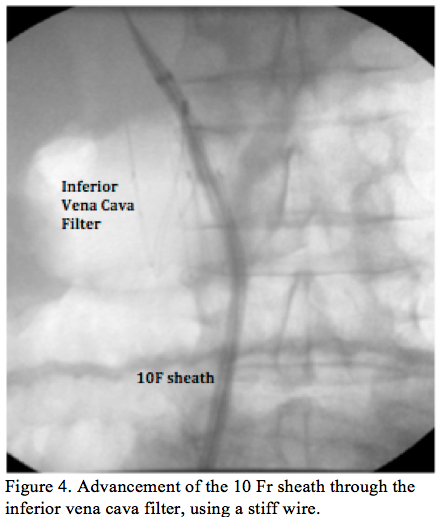

Procedure 2. Right femoral venous access was obtained and contrast media was injected to confirm the patency and absence of thrombus on the IFCV. A very-soft 0.035˝ wire (Benson wire, Parkmore Business) crossed the IVCF, over which a 6 Fr catheter was advanced, allowing the exchange for a stiff wire. A large, 90 cm, 10 Fr sheath was inserted and positioned in the right

atrium, crossing uneventfully through the IVCF (Figure 4). The Amplatzer releasing system was delivered to the right atrium via the large, 90 cm, 10 Fr sheath positioned through the IVCF, avoiding further manipulation at the level of the IVCF (Figure 5). Standard left atrial appendage closure was performed with an Amplatzer Cardiac Plug (ACP) #22 device (AGA Medical Corporation). Using the same releasing system, a #25 Amplatzer device for PFO closure was successfully implanted (AGA Medical Corporation). Continuous monitoring of the procedure with transesophageal echocardiography was performed and the correct deployment of both devices was secured (Figure 6). Careful x-ray guided retrieval of the